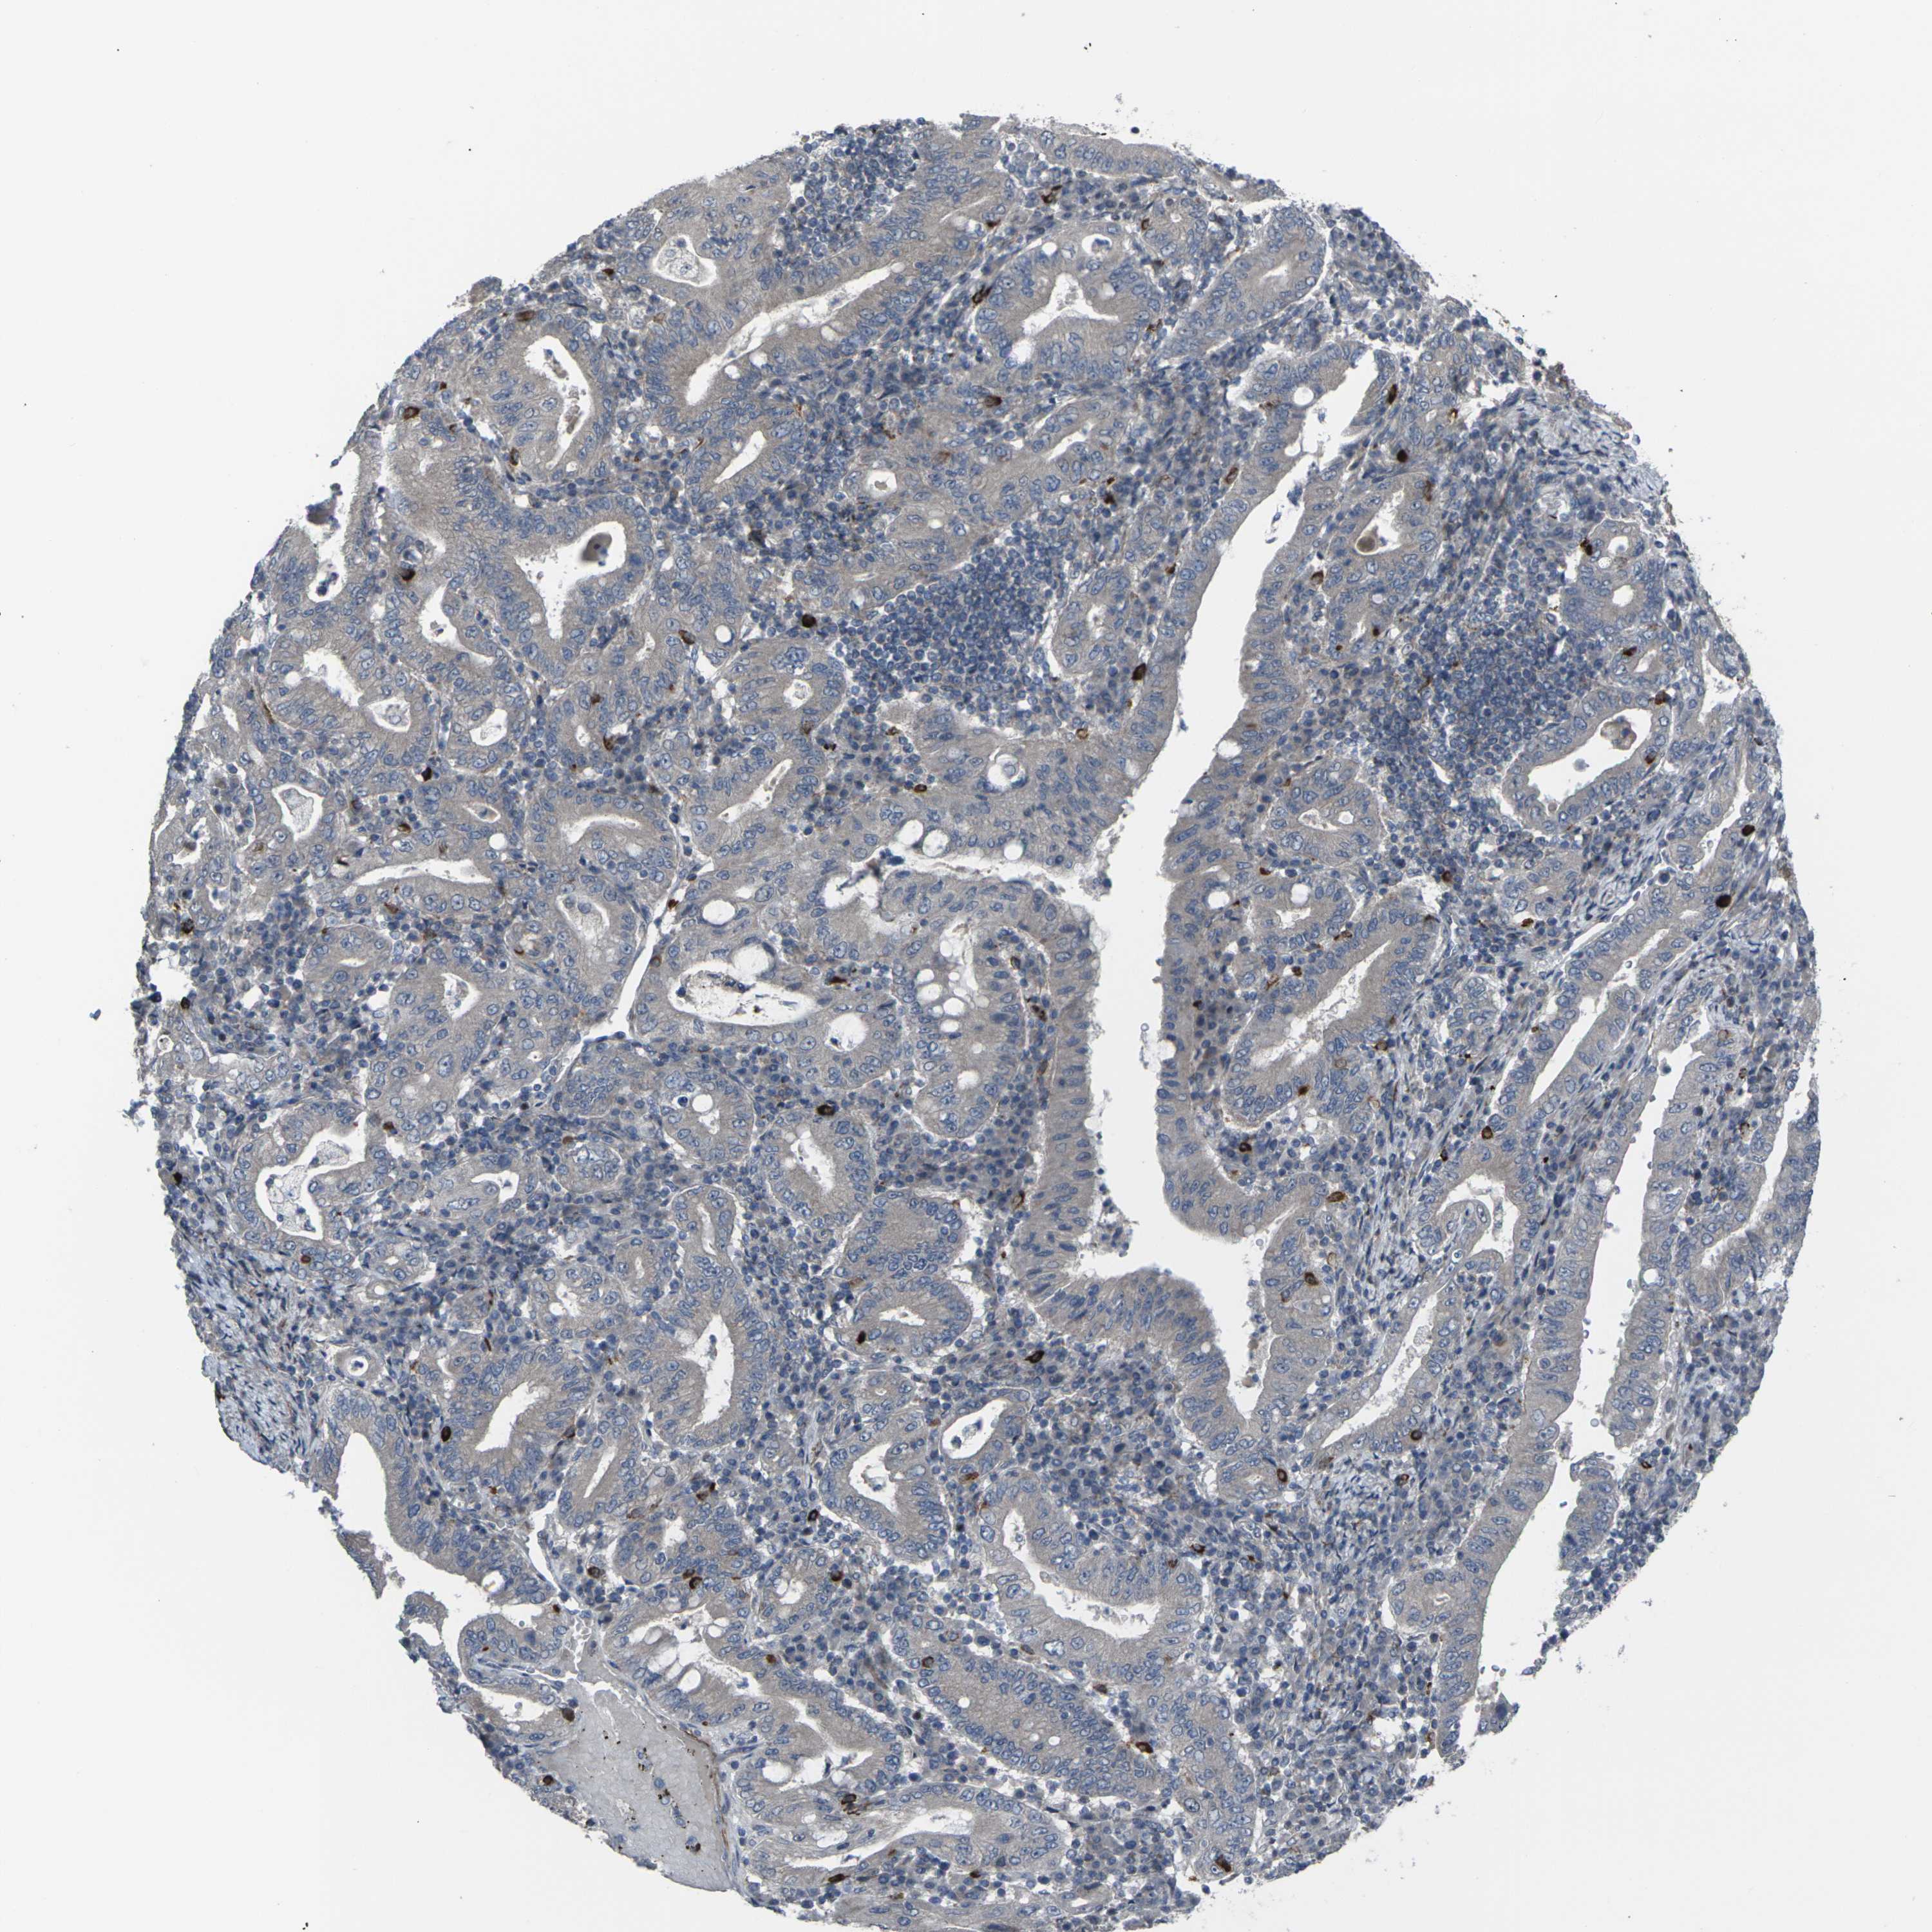

STOMACH CANCER - Protein expressioni

A mouse-over function shows sample information and annotation data. Click on an image to view it in a full screen mode. Samples can be filtered based on level of antibody staining by selecting one or several of the following categories: high, medium, low and not detected. The assay and annotation is described here.

Antibody stainingi

Antibody staining in the annotated cell types in the current human tissue is reported as not detected, low, medium, or high, based on conventional immunohistochemistry profiling in selected tissues. This score is based on the combination of the staining intensity and fraction of stained cells.

Each image is clickable and will lead to virtual microscopy that enables deeper exploration of all samples and also displays staining intensity scores, fraction scores and subcellular localization as well as patient and tissue information for each sample.

Antibody CAB011684

Staining

High

Medium

Low

Not detected

Intensity

Strong

Moderate

Weak

Negative

Quantity

>75%

75%-25%

<25%

None

Location

Nuclear

Cytoplasmic/membranous

Cytoplasmic/membranous,nuclear

Adenocarcinoma, NOS

Adenocarcinoma, High grade